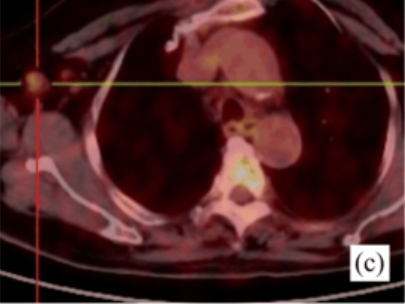

此前一位40岁的女性患者赵某某,因“发热伴皮疹1月”收入我院,患者曾于外院抗感染治疗无效,入我院后完善血常规:白细胞18.0×109/L,中性粒细胞百分比89.5%;铁蛋白4400ng/ml;血沉83mm/h;PCT0.10ng/ml;CRP82mg/L;抗核抗体谱、类风湿因子、抗“O”、肿瘤标志物、结核抗体、T-SPOT、血培养、腹部彩超等均未见异常,胸部CT提示肺部纤维灶,进一步完善骨髓穿刺、骨髓活检亦无明显异常,为明确患者发热伴皮疹原因,进一步行PET/CT检查,结果提示双侧腋窝、右侧髂外血管旁及双侧腹股沟区多发肿大淋巴结,局部淋巴结病灶FDG代谢轻度增高,考虑非特异性炎性改变。综合结合患者相关表现、检查以及排除其他病因,相关学科讨论后,初步考虑为成人still病,予以糖皮质激素治疗后皮疹消退、体温降至正常,病情平稳后带药出院。

图为患者赵女士的PET/CT融合成像显示腋窝、腹股沟淋巴结FDG摄取增高